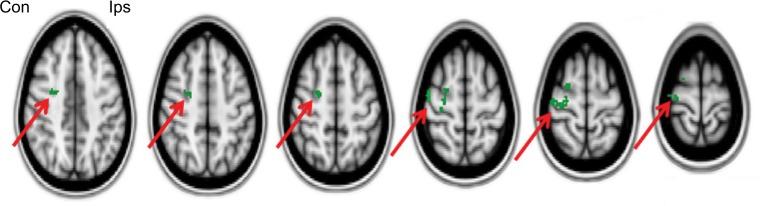

METHODS

A capsaicin 8% patch (Qutenza) treatment study was conducted on 14 patients with single limb amputation, who reported pain intensity on the Numerical Pain Rating Scale ≥4/10 for chronic stump or phantom limb pain. Pain assessments, quantitative sensory testing, and fMRI (for the lip pursing task) were performed at baseline and 4 weeks after application of capsaicin 8% patch to the amputation stump. The shift into the hand representation area of the cerebral cortex with the lip pursing task has been correlated with phantom limb pain intensity in previous studies, and was the fMRI clinical model for cortical plasticity used in this study.

The mean reduction in spontaneous amputation stump pain, phantom limb pain, and evoked stump pain were -1.007 (=0.028), -1.414 (=0.018), and -2.029 (=0.007), respectively. The areas of brush allodynia and pinprick hypersensitivity in the amputation stump showed marked decreases: -165 cm, -80% (=0.001) and -132 cm, -72% (=0.001), respectively. fMRI analyses provided objective evidence of the restoration of the brain map, that is, reversal of the shift into the hand representation of the cerebral cortex with the lip pursing task (<0.05).

自发截肢残端疼痛、幻肢疼痛和诱发残端疼痛的平均减轻分别为-1.007(=0.028)、-1.414(=0.018)和-2.029(=0.007)。截肢残端的刷状痛觉过敏和针刺超敏反应区域显著减少:分别为-165平方厘米、-80%(=0.001)和-132平方厘米、-72%(=0.001)。fMRI分析提供了脑图谱恢复的客观证据,即噘嘴任务时大脑皮质手部代表区的变化逆转(<0.05)。